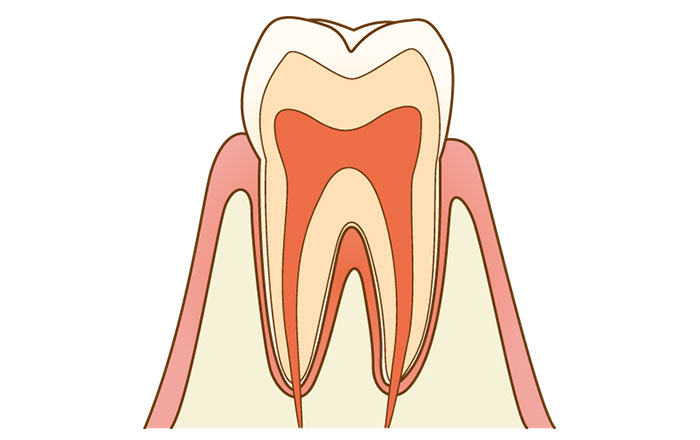

1.COのむし歯

初期むし歯や、CO(シーオー)と呼ばれる状態です。

歯の表面が溶け、健康な歯とは色が違って歯の一部が白濁します。

ですが、まだ歯に穴は空いていない状態です。

この段階では、まだ痛みはありません。